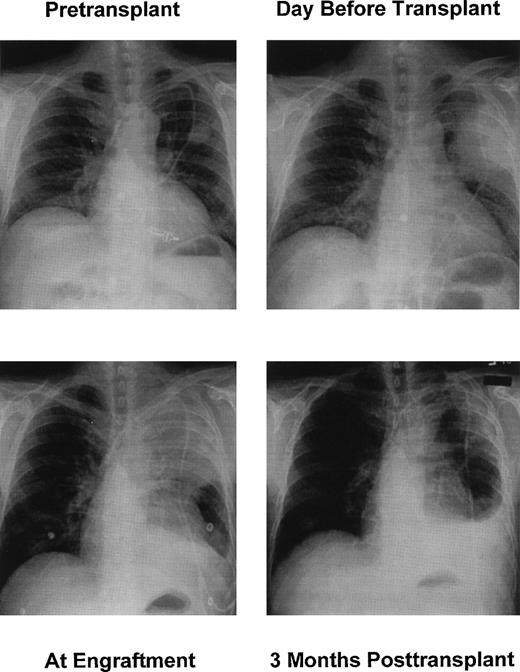

His brother was found to be HLA-A, -B, -C, -DR, -DQ matched and ABO mismatched (donor “A,” recipient “O”), and treatment with HSCT was proposed. The patient was ineligible for a conventional HSCT because of progressive pulmonary aspergillosis, renal insufficiency, and poor performance status. Therefore, he was offered a nonmyeloablative HSCT.5 On September 30, 1998 (day 0 of transplant), the patient received 200 cGy TBI at 7 cGy/min followed by infusion of unmodified G-CSF–mobilized peripheral blood stem cells (10 × 106 CD34+ cells/kg) from the brother. Postgrafting immunosuppression consisted of MMF, 15 mg/kg twice a day orally days 0 to 27, and CSP, 1.5 mg/kg twice a day intravenous days −1 to 20, and 6 mg/kg twice a day orally days 21 to 100, followed by taper over 14 days. Engraftment was prompt with an ANC of >500/μL on day 8 and platelet transfusion independence on day 13 (Fig 1). Chimerism studies done on days 14, 28, 56, 120, and 182 posttransplant using polymorphic microsatellite region 33.6 markers7 showed 99% of marrow cells and granulocytes, and 70% of T cells to be of donor origin during the first 120 days (Fig 1). By day 182, both T cells and granulocytes were 100% of donor origin. The patient had a peak bilirubin level of 13 mg/dL (90% direct) and minimal elevations of transaminases on day 10 that were attributed to high CSP serum levels and concurrent Ampho B. These resolved with CSP dose reduction. The patient was discharged to outpatient care on day 21. Skin GVHD developed on day 120 shortly after CSP was discontinued, and it responded promptly to resumption of CSP and a 2-week course of prednisone at 1 mg/kg.

Peripheral blood counts before and after HSCT (top) and microsatellite marker (region 33.6) analyses (bottom) on DNA from recipient and donor cells before transplant (lanes 1 and 2) and recipient cells after transplant (lanes 3 through 11).